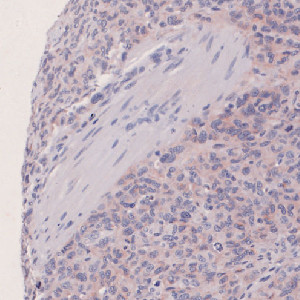

Figure 1

Nuclei surrounded by mixed COX2 staining.